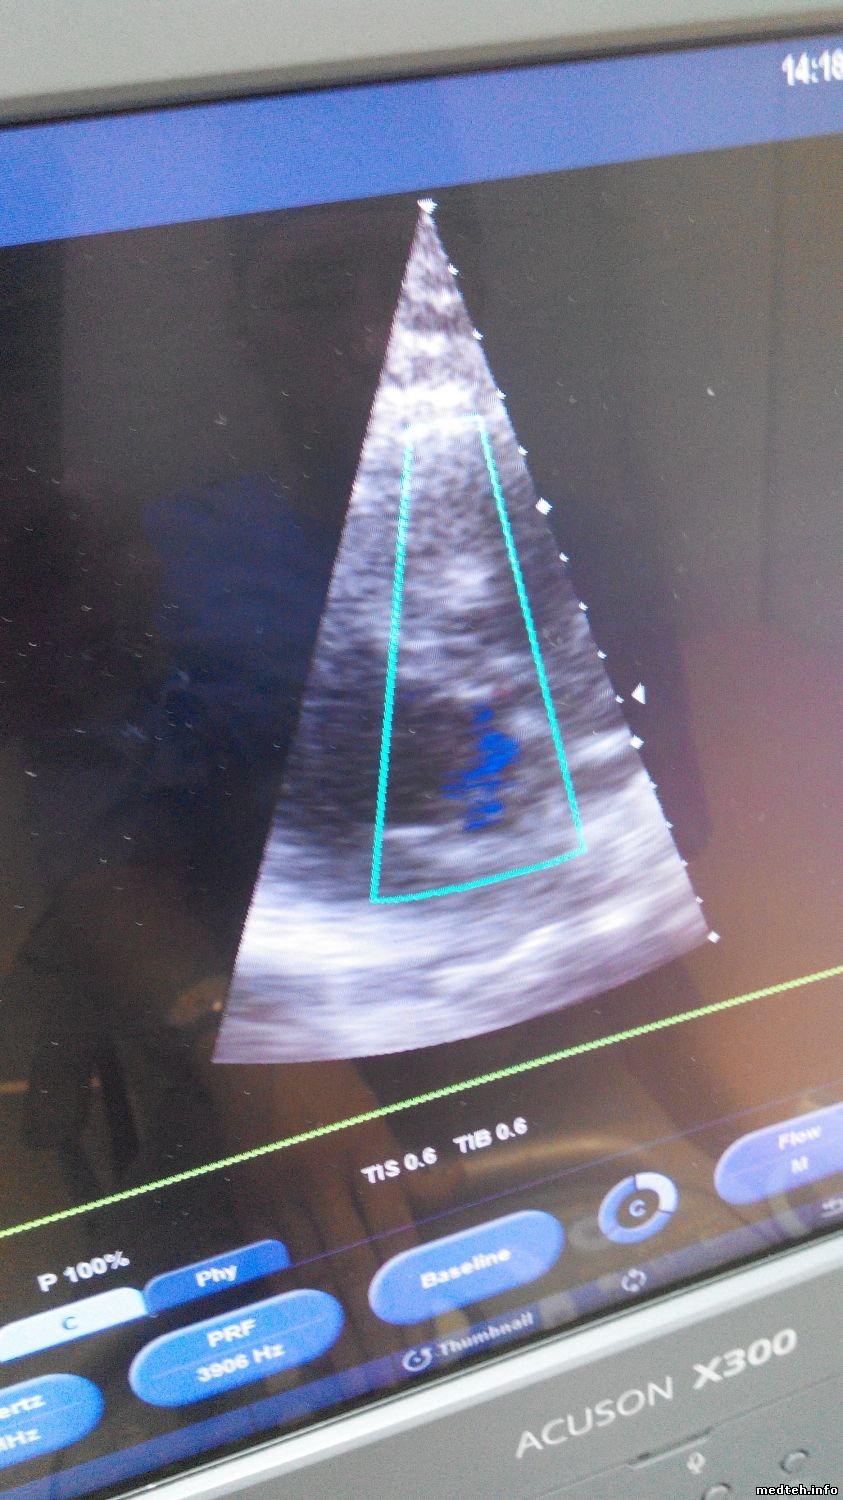

А вот как ведут эти же датчики на исправном УЗИ аппарате:

Без помех- строго по делу!!!

P.S. Даже выставлял в точности такие же настройки на своём-ремонтируемом аппарате= результат такой же, плохой ireful shok mad